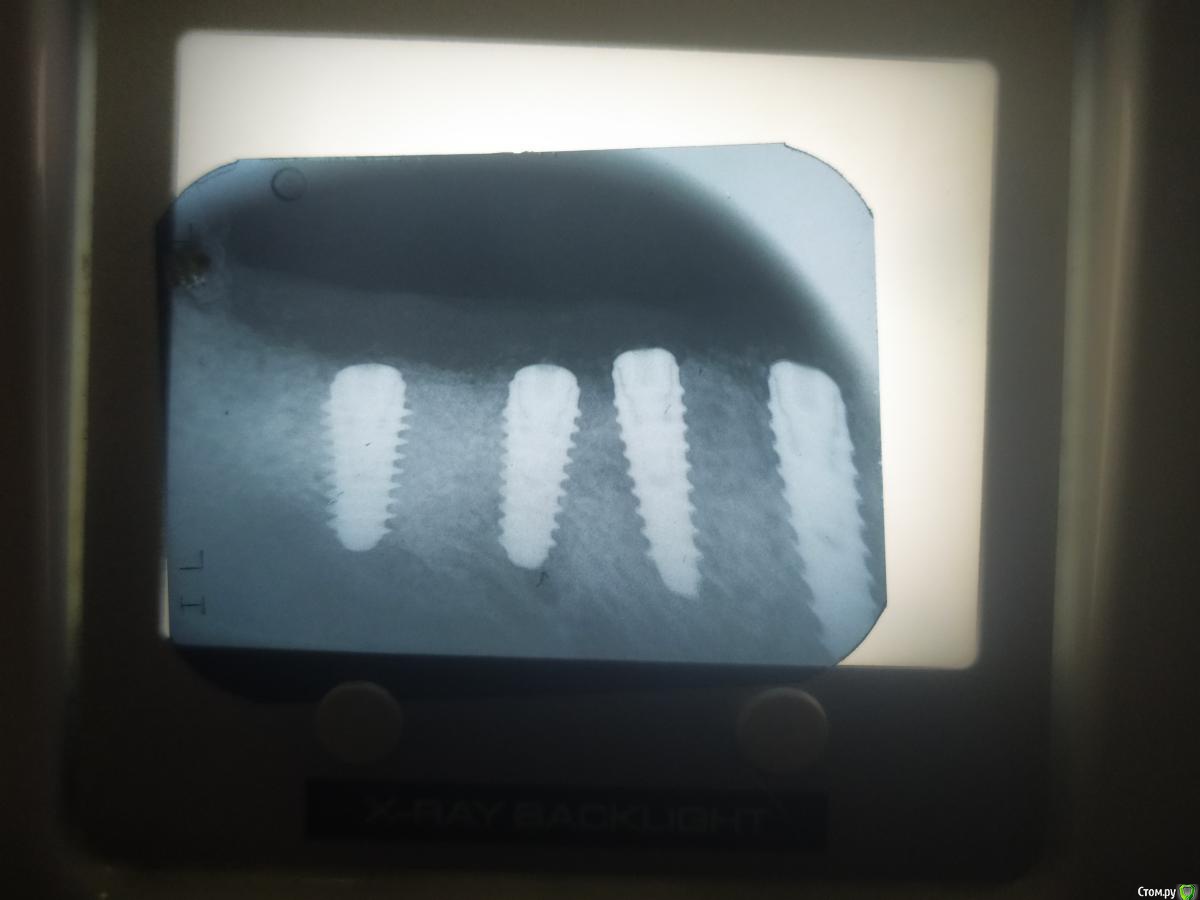

meddikus Опубликовано 9 марта, 2020 Автор Поделиться Опубликовано 9 марта, 2020 Я бы начал с прицелок, если реально секвестр - должно быть видноЕто сделано8 марта Ссылка на комментарий

meddikus Опубликовано 6 июля, 2020 Автор Поделиться Опубликовано 6 июля, 2020 (изменено) ВОПРОС СОЗРЕЛ импланти не оч близько встановленни,формики смогу поставить? Изменено 6 июля, 2020 пользователем meddikus Ссылка на комментарий

Irouil Опубликовано 6 июля, 2020 Поделиться Опубликовано 6 июля, 2020 Ну, средние немного близковато, на мой взгляд, но сейчас то уже что тут придумывать? Если все интегрировано и снимки нормальные (резорбция не больше 1.5 мм между ними) то надо протезировать, пожалуй Ссылка на комментарий